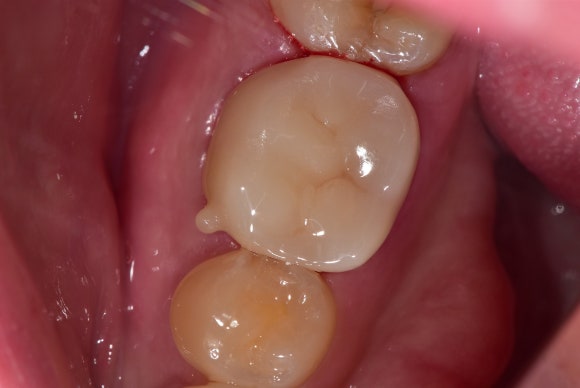

20250329

수차례 치아 내부를 청소하고 소독하기를

반복했습니다.

두 달 정도 걸려 신경치료를 마무리했습니다.

20250412

(재)신경치료의 마무리는

언제나 튼튼한 크라운입니다.

씹는 힘에 저항하며,

치아를 이중잠금으로 물샐틈 없이

보호해줍니다.